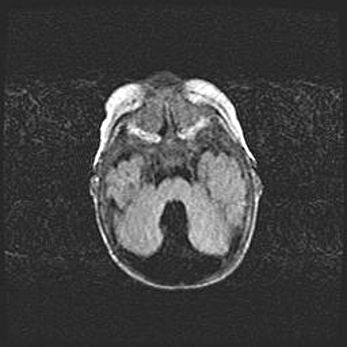

Множественные кисты обоих полушарий головного мозга, наибольшая из них в правой затылочной области. Ассиметричная атрофическая гидроцефалия.

Возраст: 7 месяцев

Вес: 5660 г

Пол: мужской

Окружность головы: 41,5 см

Срок гестации: 28-29 недель

Кисты головного мозга развиваются в результате многоочаговых некрозов вещества мозга и возникают вследствие перенесенной перинатальной инфекции, менингитов, энцефалитов, асфиксии, родовой травмы, расстройств мозгового кровообращения различного генеза. Образованию кист в веществе головного мозга плодов и новорожденных способствуют такие факторы, как высокое содержание в нем воды, недостаточная (или отсутствие) миелинизация и слабая астроглиальная реакция на повреждение.

Кисты могут сочетаться с гидроцефалией и другими поражениями головного мозга.